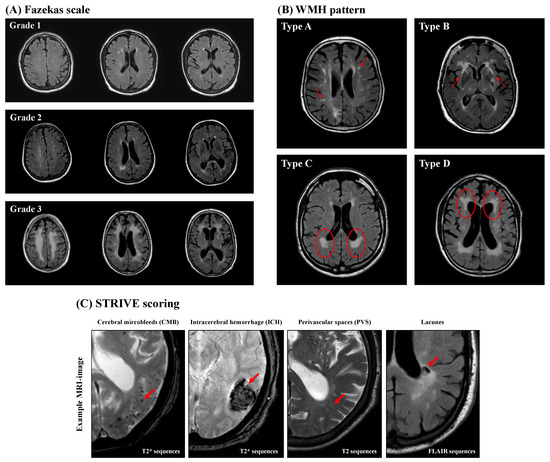

- Fazekas, F.; Chawluk, J.; Alavi, A.; Hurtig, H.; Zimmerman, R. MR Signal Abnormalities at 1.5 T in Alzheimer’s Dementia and Normal Aging. Am. J. Roentgenol. 1987, 149, 351–356. [Google Scholar] [CrossRef] [PubMed]

- Charidimou, A.; Boulouis, G.; Haley, K.; Auriel, E.; van Etten, E.S.; Fotiadis, P.; Reijmer, Y.; Ayres, A.; Vashkevich, A.; Dipucchio, Z.Y.; et al. White Matter Hyperintensity Patterns in Cerebral Amyloid Angiopathy and Hypertensive Arteriopathy. Neurology 2016, 86, 505–511. [Google Scholar] [CrossRef] [PubMed]